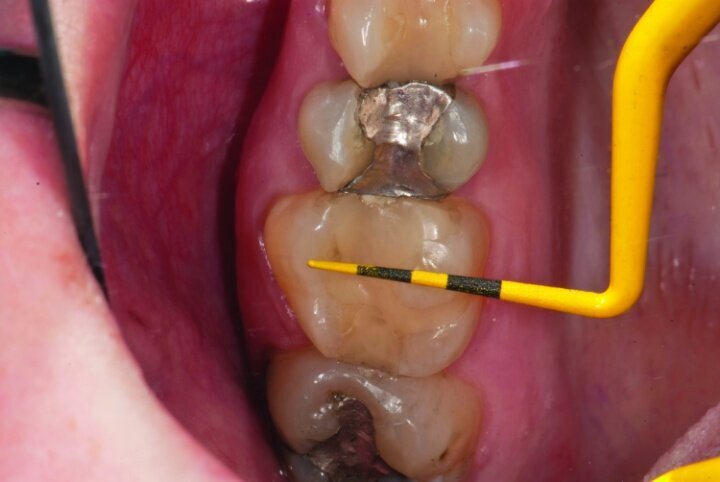

Depth guide cuts were made using a 330 bur, which has a 2 mm cutting surface (Figs. 2a–3b). This ensures 2 mm of occlusal reduction to accommodate 2 mm of material thickness on the occlusal surface of the restoration.

Gross occlusal reduction was completed using a KS7 bur to the depth cuts (Figs. 4–8b, 9c). Adequate clearance was verified with a 2 mm prep check from Common Sense Dental Products.

After gross occlusal reduction was completed, the remaining enamel ring was measured (Figs. 9a, b). The enamel rings were noted to be 1.5 mm, and the teeth were prepared for adhesively retained restorations. If the enamel rings were less than 1 mm, the teeth would have been prepared on the axial walls to create retention for cohesively retained crowns.